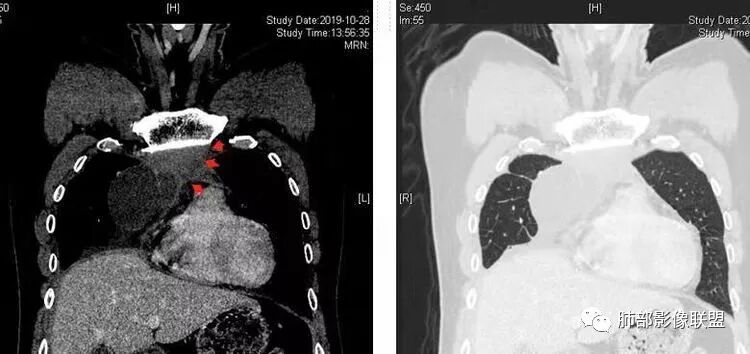

Coke with ice:囊性部分考虑包裹性积液?南边:不是积液;有间隔;张力高;而且位置有些特殊

大家仔细看看积液中的游离气体;

不是支气管,是积气;是穿刺进去的;

囊内密度不一致

我认为囊张力高,积液中的气体均在周围,外侧、下方,囊内有间隔:各腔密度不一致;提示:囊腔属于前纵隔,不是包裹性积液;现在的问题:囊腔与内侧的病灶是否是一体的

2、前纵隔内病灶囊实性混杂密度病灶,囊性病灶主要位于右侧,张力较高,有分隔影,囊壁右侧缘光整,病灶左侧实性部分边界不清明显强化,病灶肺瘤交界面大部分边界清楚,部分模糊。